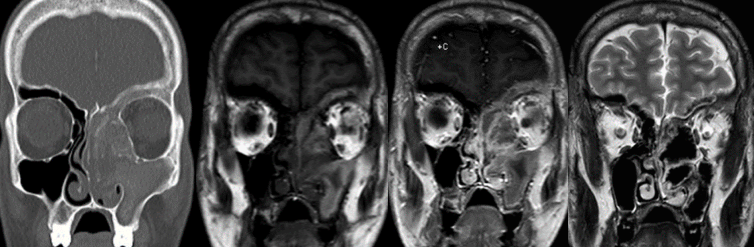

- Invasive fungal rhinosinusitis

- Orbital and optic nerve compression

- Sinonasal tumors

- Skull base tumors